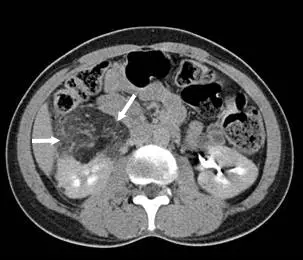

病人主訴右側腰部悶痛,血液中白血球數目正常,超音波檢查發現右側腎臟腫塊,電腦斷層檢查如附圖,下列何種診斷最正確?

本題 CT 為腹部橫切面(axial view),可見以下特徵:

- 病灶位置:右側腎臟(影像右側)見一較大的不均質腫塊,兩支白色箭頭(white arrows)分別指向腫塊的不同區域

- 密度特徵:腫塊內含有明顯的低密度(hypodense)區域,密度遠低於正常腎實質,在 CT 視窗設定下呈現接近脂肪的黑色區域,提示 Hounsfield 單位(HU) < −10,符合巨觀脂肪(macroscopic fat)

- 腫塊大小:腫塊體積較大,占據右腎大部分,造成腎臟輪廓明顯突出變形

- 增強特徵:腫塊顯示不均質增強(heterogeneous enhancement),部分區域有強化

- 對側腎臟:左側腎臟(影像左側)外觀相對正常

- 鑑別重點:腫塊內含有脂肪密度(fat attenuation)是診斷 AML 的關鍵,此發現在 renal cell carcinoma(RCC)中極為罕見(除非是脂肪瘤樣 RCC),在 xanth